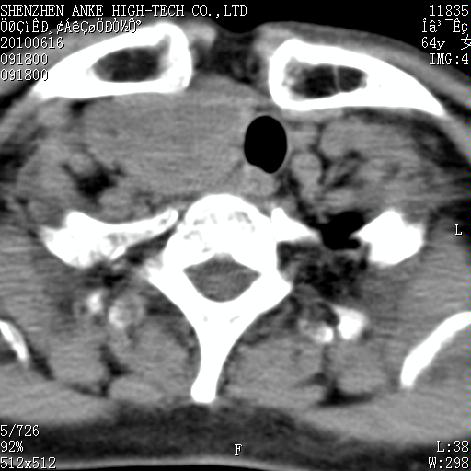

标题: CT27132:患者女,64岁,颈部及全身多处包块,现觉吞咽困难4 [打印本页]

标题: CT27132:患者女,64岁,颈部及全身多处包块,现觉吞咽困难4

右侧甲状腺占位,肿瘤可能性大,癌

右侧甲状腺癌伴右颌下腺淋巴结转移

右侧甲状腺癌伴淋巴结转移

右侧甲状腺癌伴淋巴结转移可能性大

右侧甲状腺癌伴淋巴结转移可能性大。